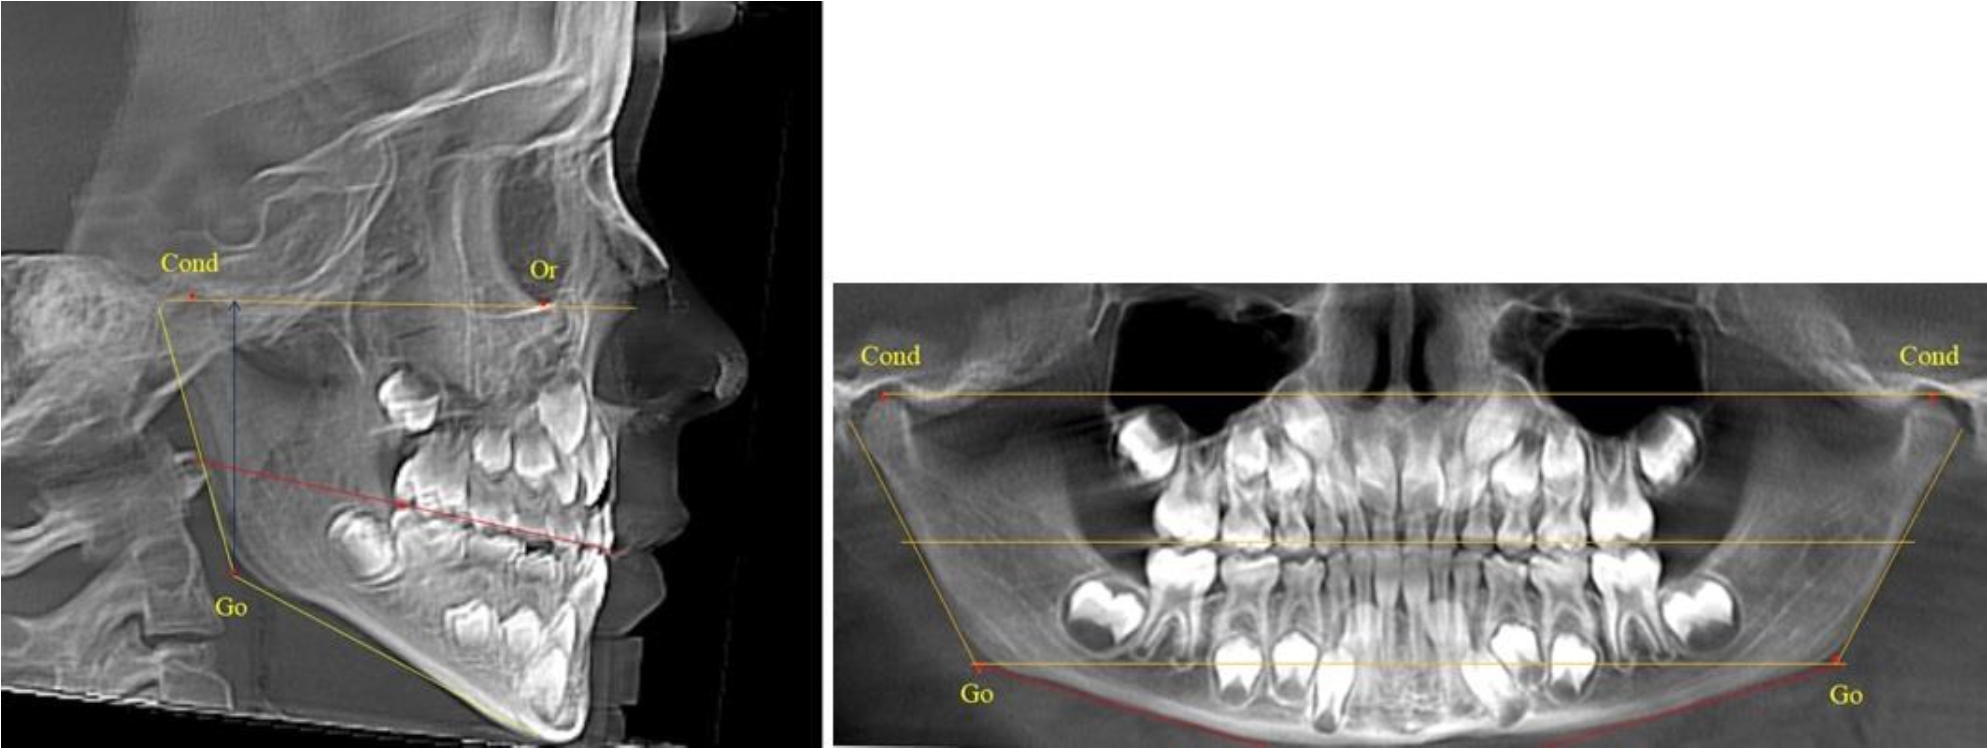

На боковых телерентгенгенограммах вершину суставной головки обозначали точкой кондиион Cond. Касательные линии к ветви и телу нижней челюсти пересекались в точке, которую обозначили Go. Точкой hPOcP обозначали дистальный бугорок нижнего второго моляра вблизи окклюзионного контура коронки. Указанный ориентир соединяли с межрезцовой точкой при построении окклюзионной линии. Высота ветви определялась расстоянием Go-Cond. Окклюзионная линия служила границей между верхней (окклюзионно-суставной) линией и нижней (окклюзионно-альвеолярной) линией.

На ортопантомограмме точки Cond соединяли между собой суставной линией Cond-Cond. Касательная к ветви нижней челюсти соединяла выступающие точки, которые соединялись в области угла и определяли положение точки гонион Go с обеих сторон, которые соединяли гониональной линией Go-Go.

Горизонтальная линя, соединяющая окклюзионные точки hPOcP, определялась как окклюзионная горизонталь.

В 1-й группе были проанализированы 7 телерентгенограмм и 7 ортопантомограмм, что составило (6,60 ± 2,41) % от числа изученных рентгенограмм. На всех парах рентгенограмм угол нижней челюсти, измеренный на телерентгенограмме, соответствовал углу, полученному при построении угла на ортопантомограмме. Окклюзионная линия практически однотипно делила ветвь на два отдела (рис. 1).

Как на ортопантомограмме, так и на телерентгенограмме высота ветви у детей в периоде сформированного прикуса молочных зубов составляла (42,21 ± 2,48) мм. При этом высота верхней окклюзионно-суставной части была (22,57 ± 1,46) мм, а нижней – (19,64 ± 1,54) мм.

Рис. 1. ТРГ и ОПТГ пациента 1-й группы

Рис. 2. ТРГ и ОПТГ пациента после прорезывания первых постоянных моляров